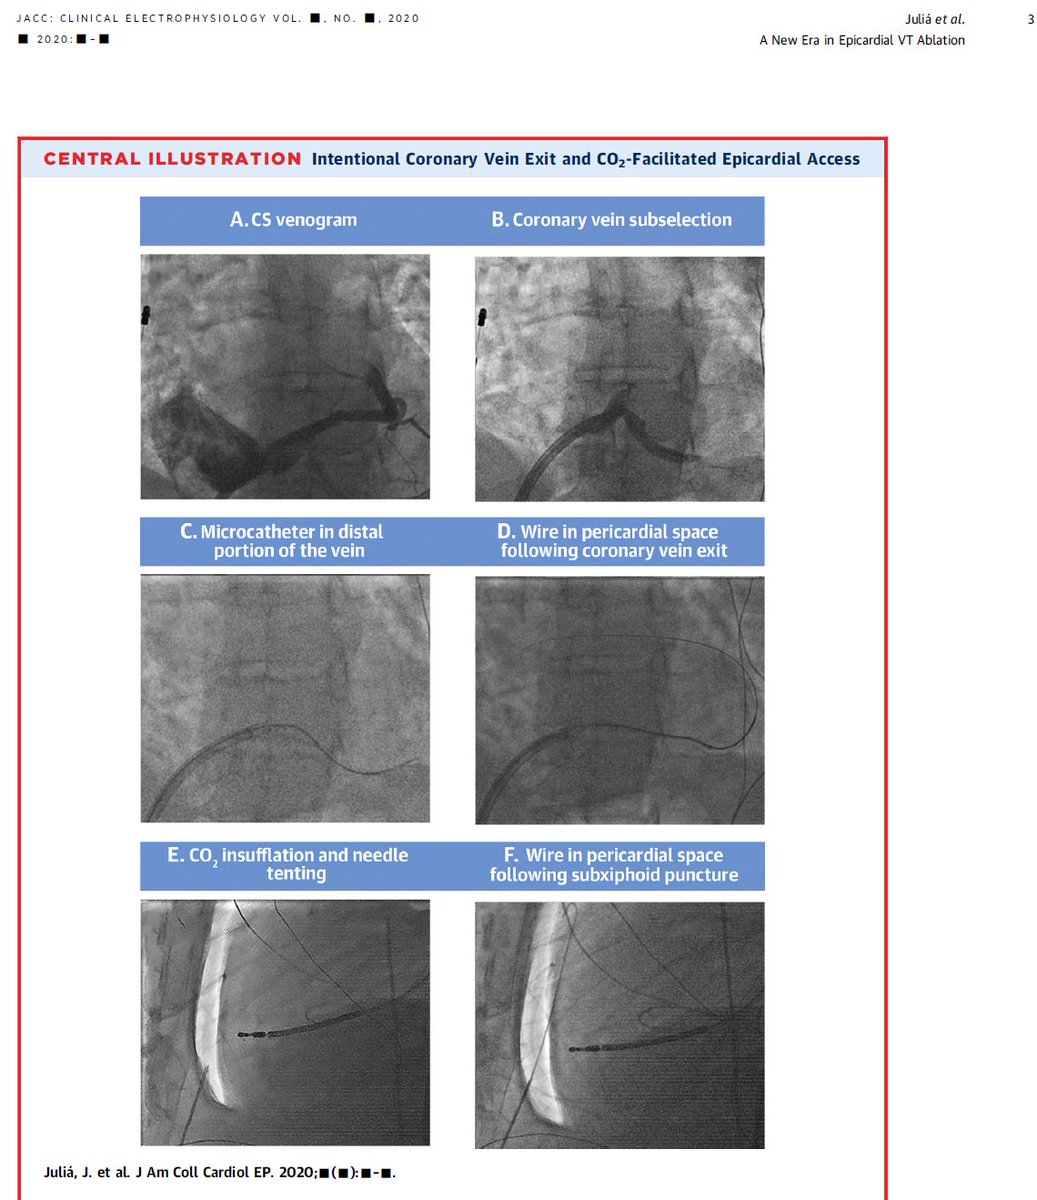

New Era of CO2 to facilitate Epicardial Access for the Ablation of Ventricular Arrhythmias? The Epi-Co2 Registry. from Juliá et al, #jaccep #epeeps